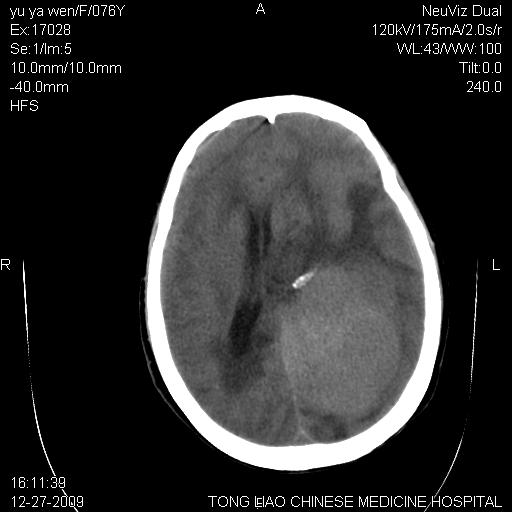

以下是引用lizhiguang在2009-12-27 19:06:00的发言:[br]脑膜瘤

以下是引用zhao_bin2008在2009-12-27 20:34:00的发言:[br]考虑脑膜瘤,伴肿瘤出血,建议增强检查

以下是引用zsl6918在2009-12-27 19:28:00的发言:[br]建议对症治疗后强化检查,考虑脑膜瘤可能性大。